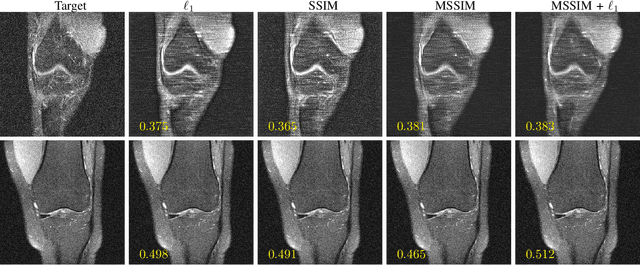

Abstract:We went below the MRI acceleration factors (a.k.a., k-space undersampling) reported by all published papers that reference the original fastMRI challenge, and then considered powerful deep learning based image enhancement methods to compensate for the underresolved images. We thoroughly study the influence of the sampling patterns, the undersampling and the downscaling factors, as well as the recovery models on the final image quality for both the brain and the knee fastMRI benchmarks. The quality of the reconstructed images surpasses that of the other methods, yielding an MSE of 0.00114, a PSNR of 29.6 dB, and an SSIM of 0.956 at x16 acceleration factor. More extreme undersampling factors of x32 and x64 are also investigated, holding promise for certain clinical applications such as computer-assisted surgery or radiation planning. We survey 5 expert radiologists to assess 100 pairs of images and show that the recovered undersampled images statistically preserve their diagnostic value.